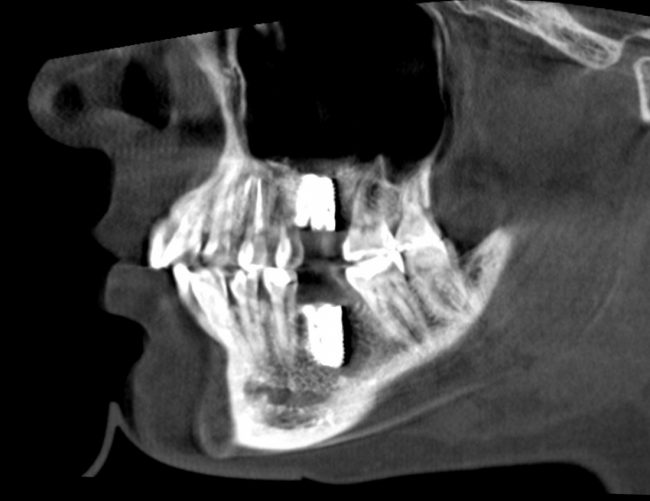

однако, в течение последующего месяца (при соответствующей терапии) рентгенологическая картина возвращается к нормальной:

Еще раз подчеркну, что причиной всего этого чаще всего является именно перфорация шнайдеровой мембраны. Если вы её не заметили во время операции — это не значит, что её нет.